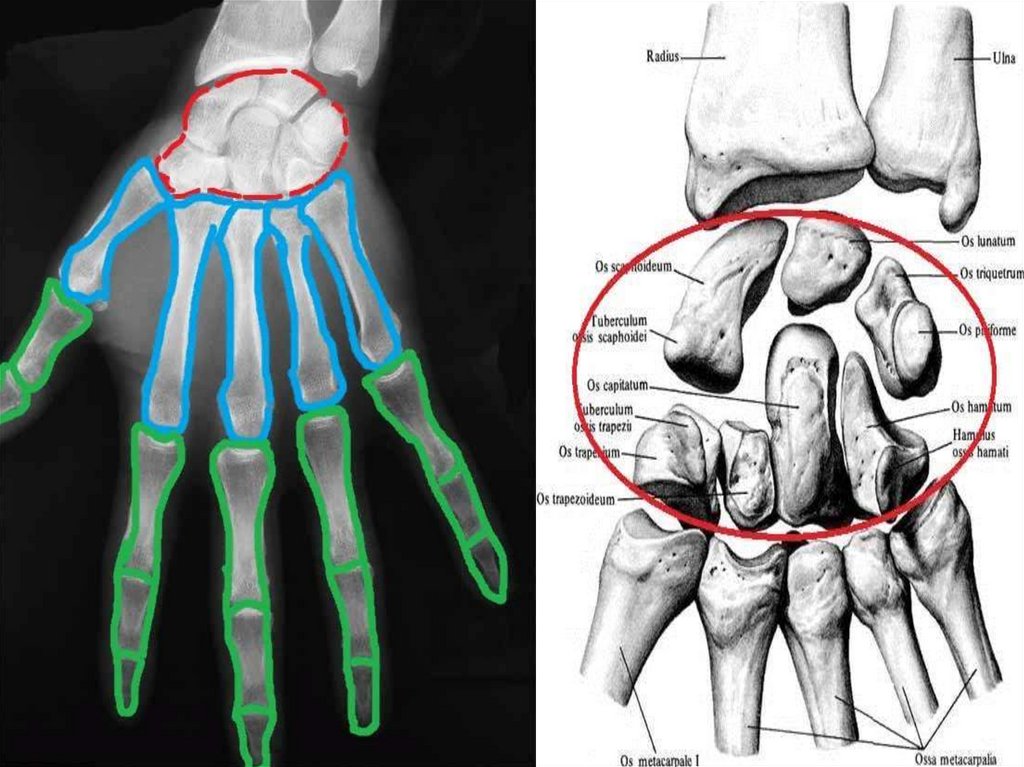

Кістки кисті – ossa manus, поділяються на зап’ясткові кістки,

Зап’ясткові кістки

розміщуються в два ряди по

4 кістки в кожному і

утворюють проксимальний

і дистальний ряди.

У верхньому

(проксимальному) ряді з

латеральної в медіальну

сторону розташовані:

1) Човноподібна кістка – має

горбок човноподібної кістки;

2) Півмісяцева кістка;

3) Тригранна кістка;

4) Горохоподібна кістка.

38.

39.

Човноподібна кістка стоїть першою (зі сторони великого пальця) у

проксимальному ряді кісток зап’ястка і являється самою великою

кісткою верхнього ряду. Її горбик пальпується зі сторони долонної

поверхні кисті вище головки першої п’ястної кістки.

Півмісяцева (2) та Тригранна (3) кістки доповнюють цей ряд;

човноподібна та півмісяцева з’єднуються з променевою кісткою,

тригранна з суглобовим диском. Горохоподібна (4) кістка в

утворенні променевозап’ясткового

суглоба участі не

приймає та сполучається з верхньою

поверхнею тригранної кістки.

1

3

2

4

40.

41.

Нижній, дистальний ряд складається з кісток які розташовані з

латеральної в медіальну сторону:

- кістка-трапеція (має горбок

кістки-трапеції);

- трапецієподібна кістка;

- головчаста кістка;

- гачкувата кістка (має гачок

гачкуватої кістки).

42.

Кістка-трапеція перша в дистальному ряді кісток зап’ястка і

з’єднується з першою п’ястною кісткою. Трапецієподібна (2)

розміщується між трапецією та головчастою кісткою. Головчаста (3)

розміщується в середині нижнього ряду і являється найбільшою із

кісток зап’ястка. Гачкувата (4) кістка виділяється зі сторони

долонної поверхні своїм гачкоподібним відростком.

утворюють

борозну зап’ястка.

43.

44.

Кістки зап’ястка – ossa carpi

1. Човноподібна кістка – os scaphoideum

2. Півмісяцева кістка – os lunatum

3. Тригранна кістка – os triquetrum

4. Горохоподібна кістка – os pisiforme

5. Кістка-трапеція – os trapezium

6. Трапецієподібна кістка – os trapezoideum

7. Головчаста кістка – os capitatum

8. Гачкувата кістка – os hamatum

П’ясткові кістки – ossa metacarpi s. metacarpalia

Cкладаються з п’яти коротких кісток, не мають назв, кожна з яких

має основу п’ясткової кістки, тіло п’ясткової кістки і головку

п’ясткової кістки.

- Перша п’ясткова кістка має на основі характерну сідлоподібну

поверхню;

- Друга – глибоку вирізку;

- Третя п’ясткова кістка має шилоподібний відросток;

- Четверта – виражені суглобові поверхні;

- П’ята – горбистість.

На обернутих одна до одної поверхнях основ ІІ-V п’ясткових

кісток містяться суглобові поверхні для з’єднання між собою.

Кістки (фаланги) пальців – phalanges digitorum

Cкладаються з основи фаланги, тіла фаланги і головки фаланги.

На головці фаланги міститься блок фаланги.

ІІ-V пальці кисті мають проксимальну фалангу, середню фалангу і

кінцеву фалангу.

Великий (перший) палець кисті - складається лише з

проксимальної фаланги і кінцевої фаланги.

Проксимальна фаланга

має на основі ямку,

середня – дві ямки,

кінцеві фаланги на

дистальному кінці

мають горбистість

кінцевої фаланги,

на якій розміщується

ніготь.